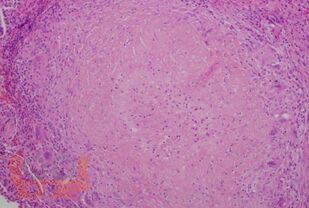

Le manuel présente des données modernes sur la tuberculose orofaciale. Les questions d'étiologie, de classification, de pathogenèse, de facteurs de risque, de clinique, de diagnostic, de diagnostic différentiel sont décrites en détail. Un algorithme d'examen des patients suspects de tuberculose orofaciale et les principes de son traitement sont présentés.

Compte tenu de la rareté du développement de la tuberculose de cette localisation, le matériel de manuel est illustré par les données cliniques des patients atteints de tuberculose orofaciale vérifiée, qui sont accessibles au public et publiées sur Internet dans des revues spécialisées.